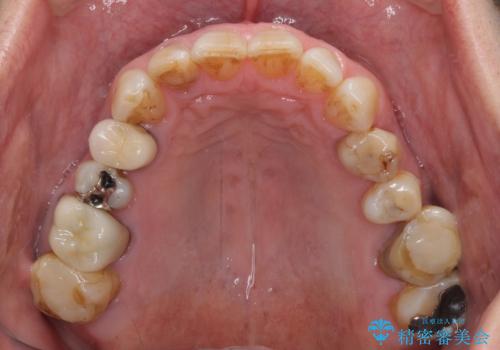

憧れの白い歯に 全顎セラミック治療

- 60歳を越え、黄ばんだ前歯をセラミッククラウンできれいな口元にしたいとのことで来院された患者様です。

診察したところ、前歯は反対咬合であり、その影響で抜歯が必要な奥歯があることが分かりました。

抜歯が必要な奥歯は、インプラント並びにブリッジにより補綴を行い、上下前歯は反対咬合を改善させるように補綴治療を行うこととしました。

健全な歯を削ってセラミッククラウンに置き換えることは、本来避けるべき治療と考えますが、今回は①患者様が60歳を越えていること、②要改善の咬合により抜歯が必要な奥歯があること、③反対咬合の前歯改善の手段としてセラミック治療が選択肢にあることなどから、全顎的なセラミック治療を行うこととしました。